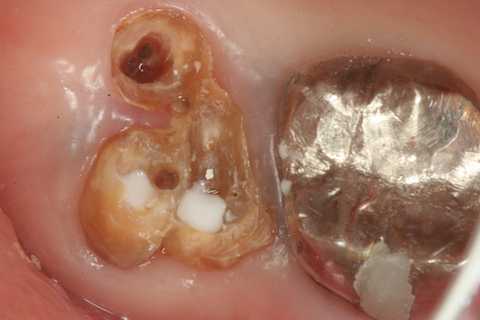

今日の抜歯再植術シリーズ39.2 2025.11.15